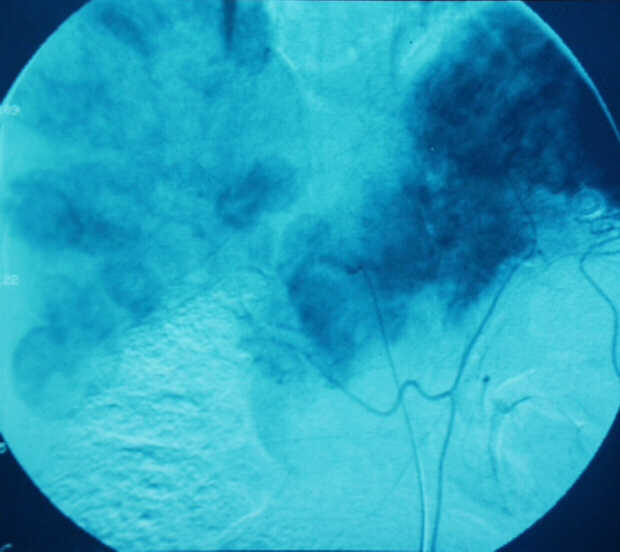

Diagnosis: Angiography

Giuseppe Morelli Coppola, Raffaella Niola, Franco Maglione

Unità Operativa di Radiologia Vascolare ed Interventistica, Azienda Ospedaliera "A. Cardarelli". Napoli, Italy